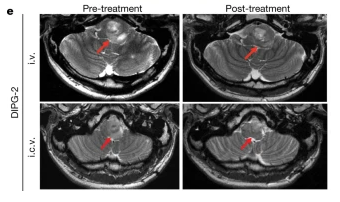

但治疗2-3个月后,肿瘤复发并再次出现之前的症状。因此通过脑室给药(ICV)再次进行GD2-CAR T治疗。两周后,症状缓解,面部力量近乎正常,能进行长距离独自行走,MRI扫描显示,肿瘤体积减小了27%。